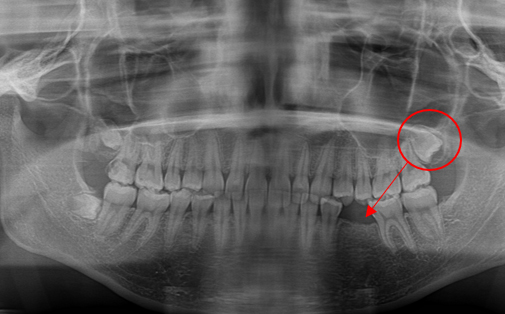

抜歯した親知らずを移植(1)

Before

After

左上の親知らずの歯を移植しました。20代前半の症例です。

ご自身の歯のため親和性が高く、移植後も不自由なく機能しています。